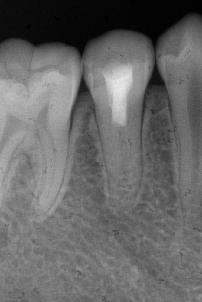

治疗前